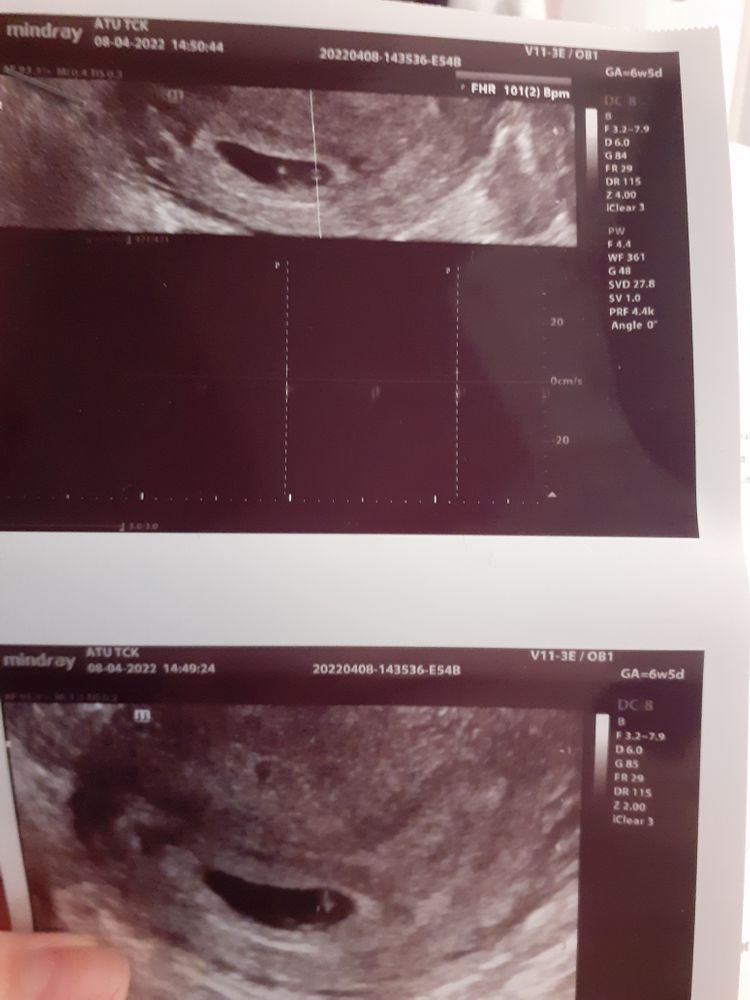

Christina, всё-таки поехала я после работы на УЗИ, заодно и доплер сделали)) не могла я успокоиться😅 все хорошо с малышом, доплер хороший, шейка хорошая, только умеренный гипертонус миометрия по задней стенке. Плацента уже 3 см от внутреннего зева, поднимается хорошо)) малыш все также опережает срок на неделю😊 наверное будет тоже не маленький, как и старший))

Мама сыночков

Анечка, всё-таки поехала я после работы на УЗИ, заодно и доплер сделали)) не могла я успокоиться😅 все хорошо с малышом, доплер хороший, шейка хорошая, только умеренный гипертонус миометрия по задней стенке. Плацента уже 3 см от внутреннего зева, поднимается хорошо)) малыш все также опережает срок на неделю😊 наверное будет тоже не маленький, как и старший))